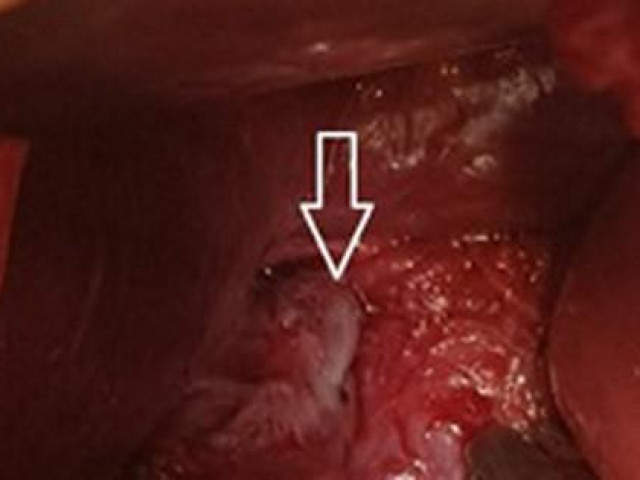

Ban đầu các bác sĩ tìm cách đưa mũi khoan ra ngoài bằng đường nội soi nhưng nó nằm quá sâu trong phổi. Lúc này, Jozsi bắt đầu cảm thấy lo lắng, đặc biệt là sau khi được thông báo không thể lấy mũi khoan ra ngoài và có thể cần phải cắt bỏ 1 phần phổi.

May mắn thay, tiến sĩ Alraiyes và nhóm của mình đã nghĩ ra cách sử dụng phương pháp nội soi phế quản robot, thường được sử dụng để phát hiện các nốt ung thư phổi nhỏ. Quy trình kéo dài 90 phút và mũi khoan đã được lấy ra.